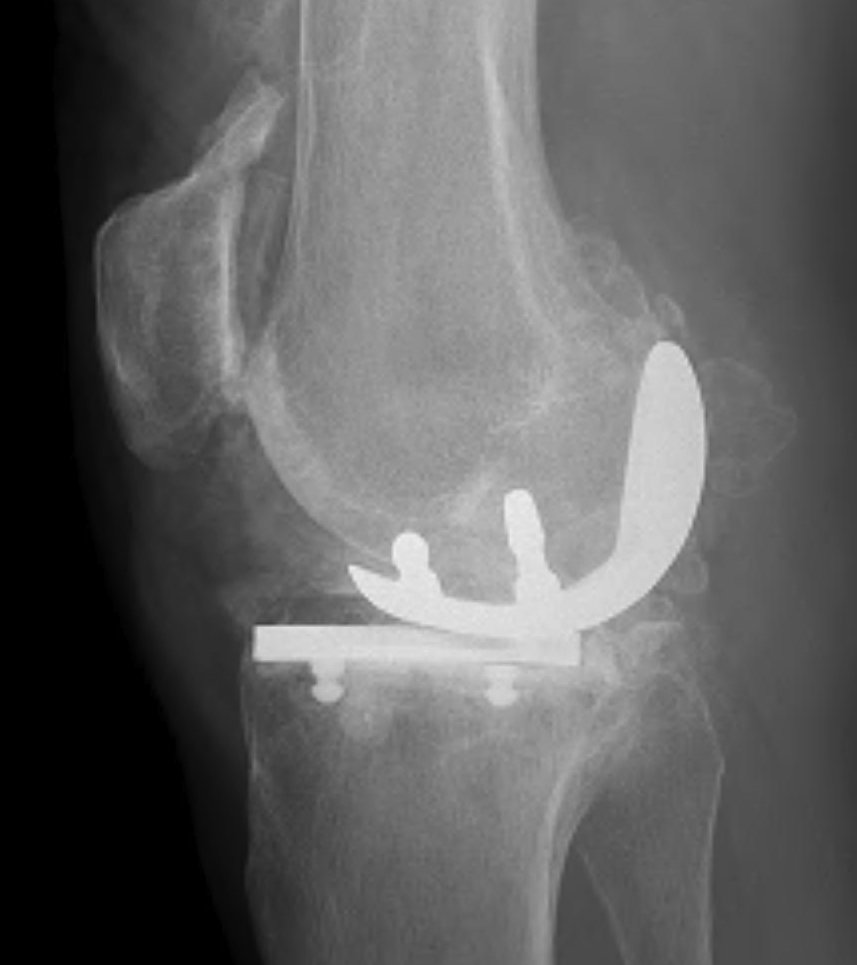

Patient 1

Patient 2